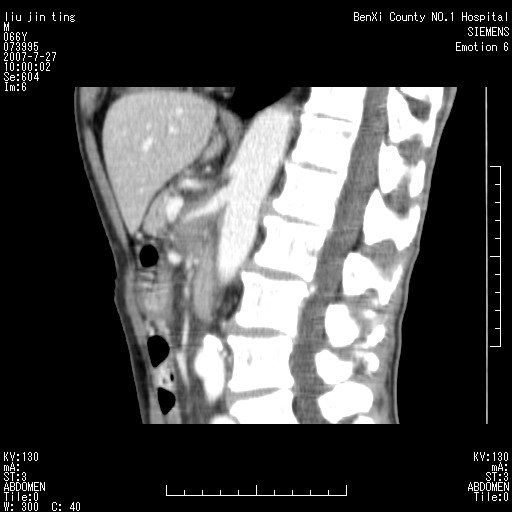

腹痛,背痛,无恶心呕吐,不黄,彩超示胰腺钩癌,ct扫描病灶平扫30-40hu,增强后动脉期40--60hu,静脉期50-68hu,真的是钩突上的么?您要试一试么?

沿着肠系膜上动脉呈匍匐性生长的软组织肿块,形态不规则,包绕肠系膜上动脉,呈明显强化,考虑来源于肠系膜的恶性肿瘤

钩突是正常的,只见腹膜后淋巴结的肿大,考虑淋巴瘤或转移可能。

腹膜后占位性病变,首先考虑肿大淋巴结。